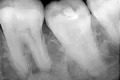

Сейчас нахожусь в Таиланде. Прошел обследование у дантиста. Мне на основании снимка поставили диагноз: глубокий кариес. Рекомендовали одно из трех: удаление зуба; чистка корневого канала; временная пломба.

У Вас однозначно глубокий кариес, переходящий в пульпит, так как поражение слишком глубокое.

В любом случае, этот недуг лечится в два посещения с удалением нерва, и соответственно ― с временной пломбой. В любом случае, зуб спасти и оставить живым нельзя.